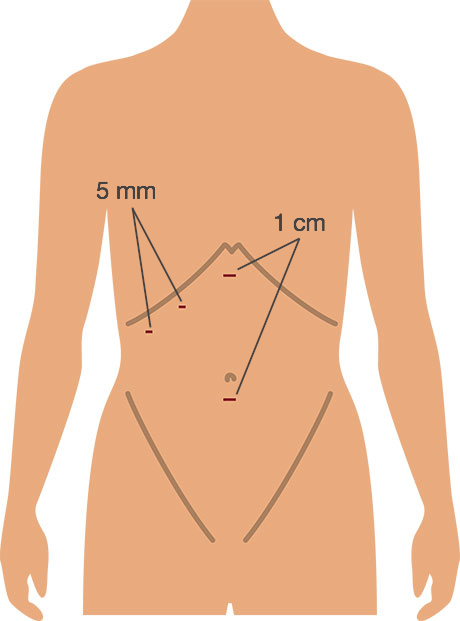

What does a keyhole operation to remove the gall bladder involve?Cholecystectomy is usually carried out by the laparoscopic (‘key hole’) method. Three or four small cuts are made in the abdomen. Each of these cuts is generally no more than 1 cm in length. The abdomen is then blown up with carbon dioxide (CO2) gas. This lifts the abdominal wall upwards, and gives the surgeon space to operate. The gall bladder is removed using a special laparoscopic camera and instruments. The operation usually takes 30 to 90 minutes. At the end of the operation the carbon dioxide gas is let out.